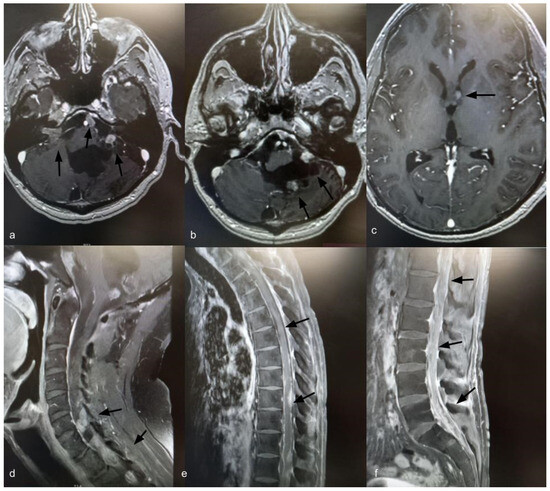

Fourteen years after the initial surgery, at age 40, the patient developed acute right-sided hearing loss. Brain and spinal MRI demonstrated multiple posterior fossa lesions, diffuse spinal leptomeningeal enhancement, and multiple solid lesions throughout the entire spine (Figure 3), consistent with LMD. Surgery was not pursued, as no clinical benefit was anticipated. The patient underwent craniospinal irradiation comprising 30 sessions. At the three-month follow-up, MRI showed stable disease. He subsequently developed symptomatic communicating hydrocephalus requiring ventriculoperitoneal shunt placement. CSF cytology was negative for neoplastic cells. Six months after radiotherapy, with no radiological improvement, systemic chemotherapy was initiated with carboplatin (600 mg), etoposide (175 mg), and vincristine (2 mg), administered every 28 days for six cycles. Thirty months after the diagnosis of LMD, the patient remains alive with stable brain and spinal lesions with no evidence of new disease (Figure 4).

Figure 3.

Axial T1-weighted brain MRI with gadolinium showing ventriculomegaly and multiple posterior fossa lesions at the right internal auditory canal, left cerebellopontine angle, prepontine cistern, and left frontal ventricular horn (a–c) (black arrows). Sagittal T1-weighted spine MRI with gadolinium showing leptomeningeal dissemination (d–f) (black arrows).